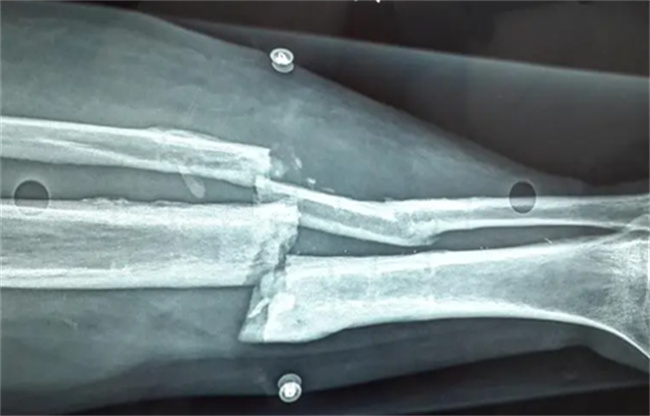

骨折和骨挫伤是骨科常见的两种损伤情况,它们的本质区别在于骨是否断裂。骨折是骨骼断裂的情况,而骨挫伤则是骨骼受到猛烈冲击或挤压导致骨骼表面产生碎裂。具体来说,骨折是指骨骼因受外力作用,而发生断裂的情况,骨折的类型有完全性骨折、不完全性骨折、开放性骨折等。骨折可以分为外伤性骨折和病理性骨折两类。外伤性骨折通常是因为肢体受到撞击、扭伤、摔倒、交通事故等外力导致的,而病理性骨折则是由于肿瘤、骨质疏松、骨髓炎等病理原因导致的。而骨挫伤则是指骨骼因受外力作用,而出现骨骼表面产生碎裂的情况,也称为骨皮质挫伤或骨皮质压迫性骨折。骨挫伤的症状比较轻微,通常不会出现明显的骨折症状,如骨移位等。